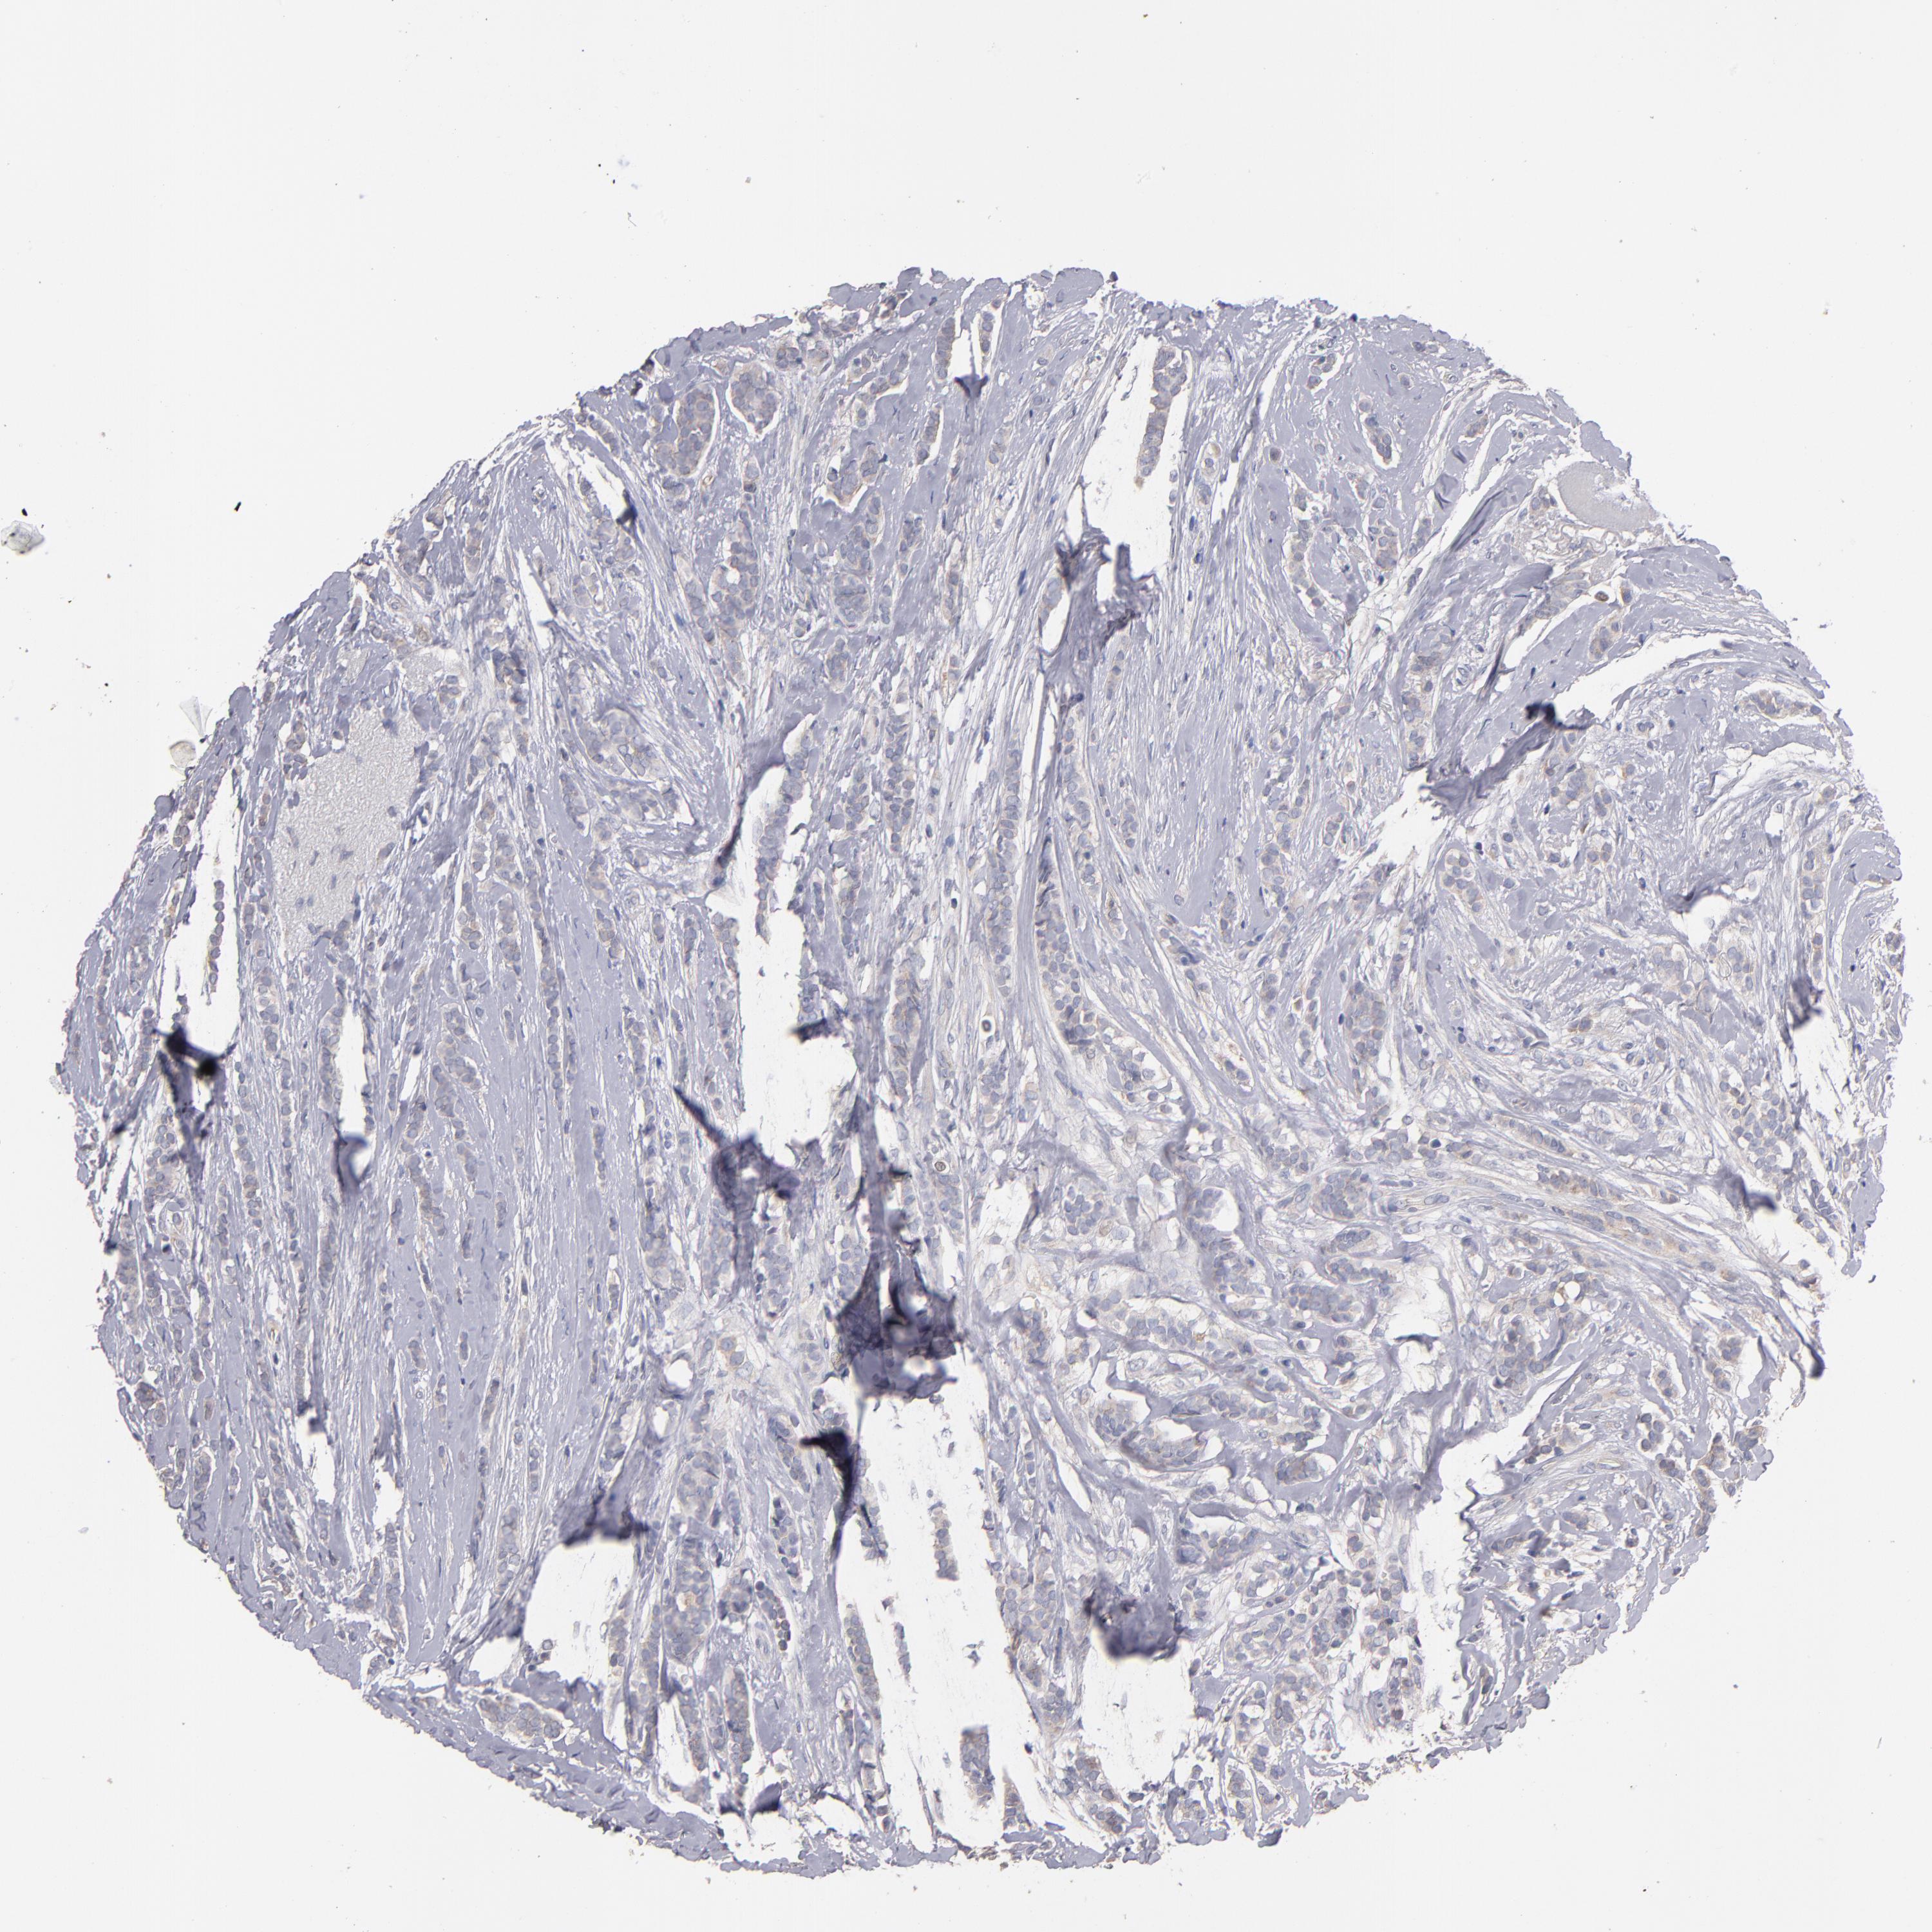

CANCER BREAST CANCER Show tissue menu

Breast cancer

Human cancer

DACT1 is not prognostic in Breast Invasive Carcinoma (TCGA)